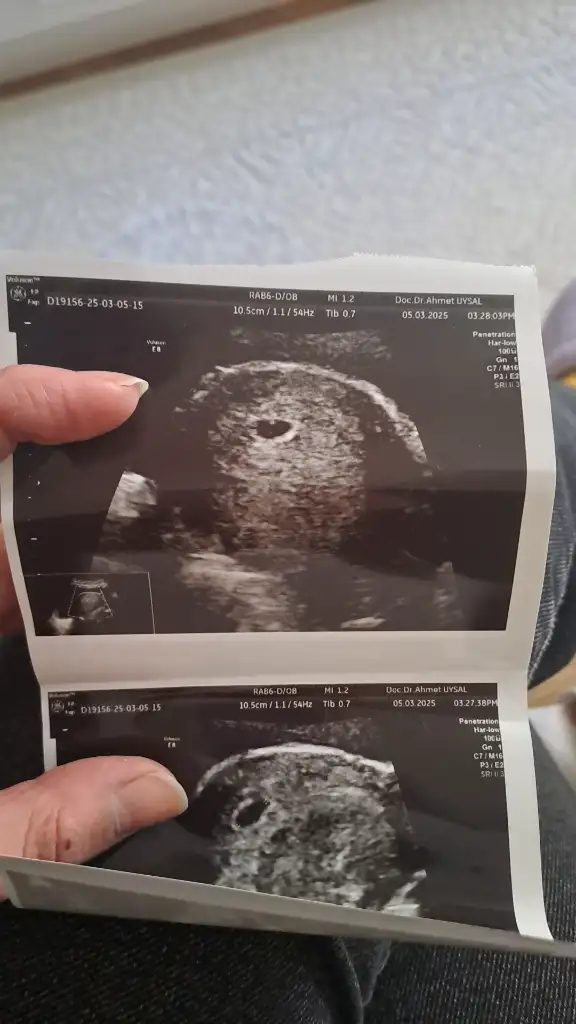

Korkma hiç devletin cihazları iyi değil o yüzden göremedi ben sana aradaki farkları atıyım da bakYaa öyle ağrım yok çok şükür arada hafif oluyor uzanınca geçiyor hemen çok rahatladım ya Allah razı olsun canım benim![]()

Aaa gerçektenKorkma hiç devletin cihazları iyi değil o yüzden göremedi ben sana aradaki farkları atıyım da bakbiri devlet biri özel 1 gün arayla

Kız ben önceki bebekte 7 haftalıktım kalp atışı dinlemeye devlete gittim bana boş gebelik dediAaa gerçektenfark çok ay iyi ki varsınız ya